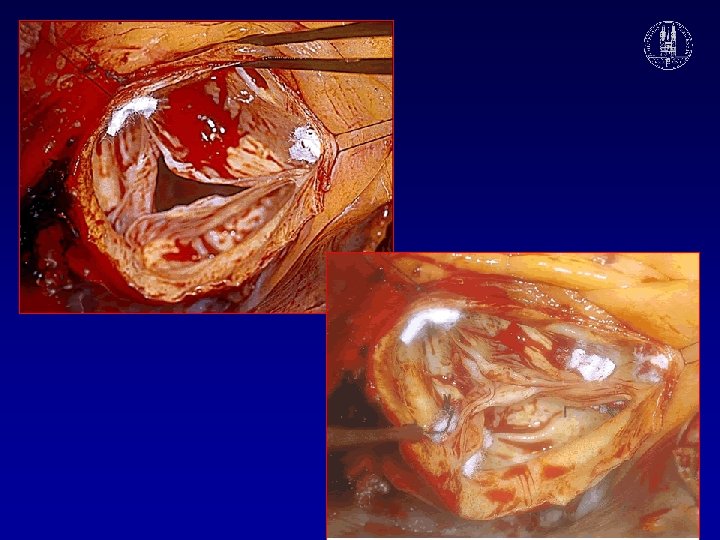

Loss of commissural support due to dilatation of sino-tubular junction

DANGEROUS TECHNIQUE, TO BE AVOIDED

Cusp shortening with 7 -0 PTFE suture